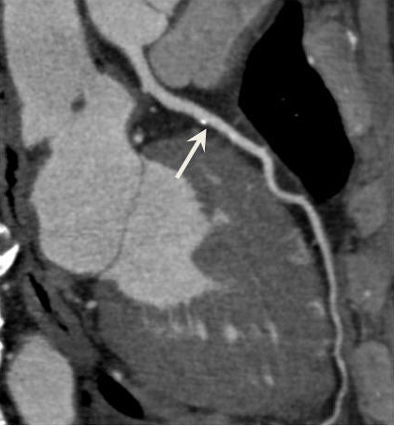

Breath-hold CT and free-breathing CT

Image quality comparison shows no significant differences between breath hold and free-breathing techniques.